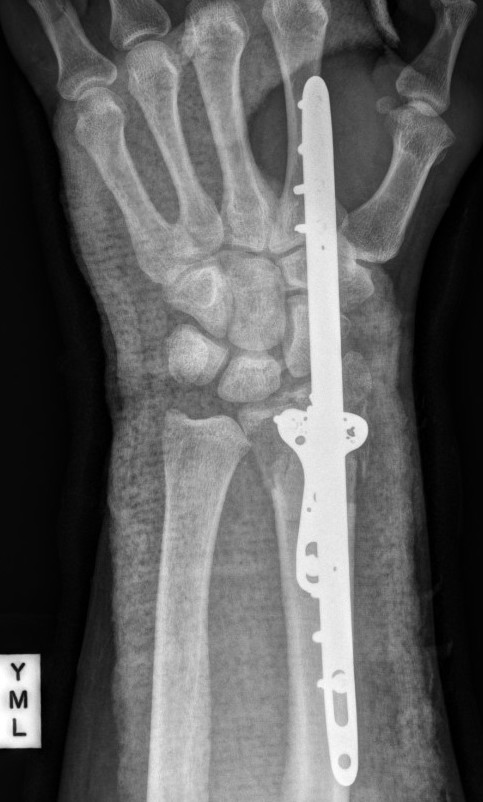

![]() |